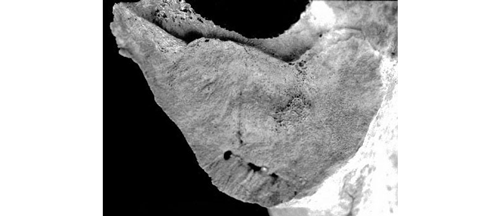

SSPIB (Modification de la Surface Articulaire)

Avec l’âge, la texture de la surface articulaire se modifie (granulation, aspect de papier de verre) et des porosités (perforations de 1 à 10 mm) se forment.